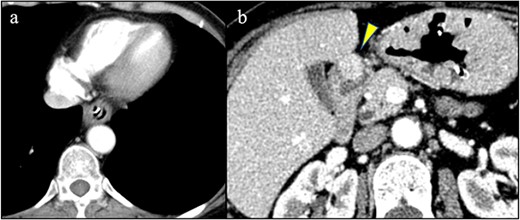

A 58-year-old woman with severe stricture of the lower esophagus was referred to our institution. She had been receiving medication to treat GERD at multiple facilities for the past 5 years. Six months prior to the referral, she underwent laparoscopic esophageal repair for esophageal rupture (Fig. 1a). After the rupture, she eventually presented with NE (Fig. 1b), a condition that consequently led to severe stenosis of the lower esophagus (Fig. 2). Multiple biopsies did not confirm any malignancy in the esophagus, and endoscopic balloon dilatation temporarily enabled endoscopic observation of the gastro-duodenum, which had no significant abnormal findings, but failed to relieve the constriction. Computed tomography revealed a 10-mm hypervascular mass on the anterior wall of the duodenum, suggestive of a gastrointestinal stromal tumor (Fig. 3); there were no findings suggestive of esophageal malignancy. Pathological diagnosis of the duodenal mass could not be determined because the endoscope used for endoscopic ultrasound-fine needle aspiration could not pass through the esophageal stricture.

(a) No findings in the esophagus suggested malignancy. (b) A hypervascular mass was detected on the anterior wall of the duodenum (arrowhead).